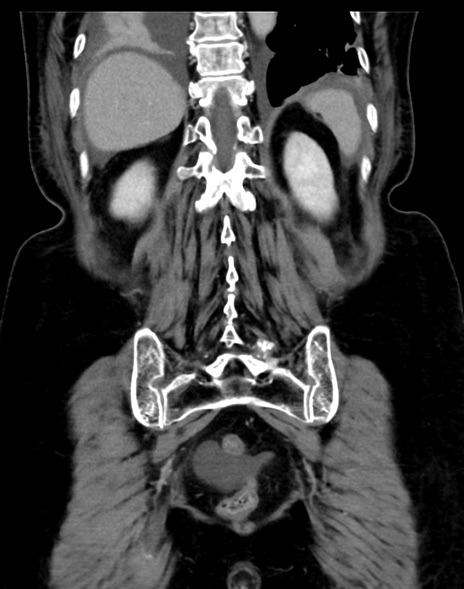

症例13 CT(冠状断像)1日半後